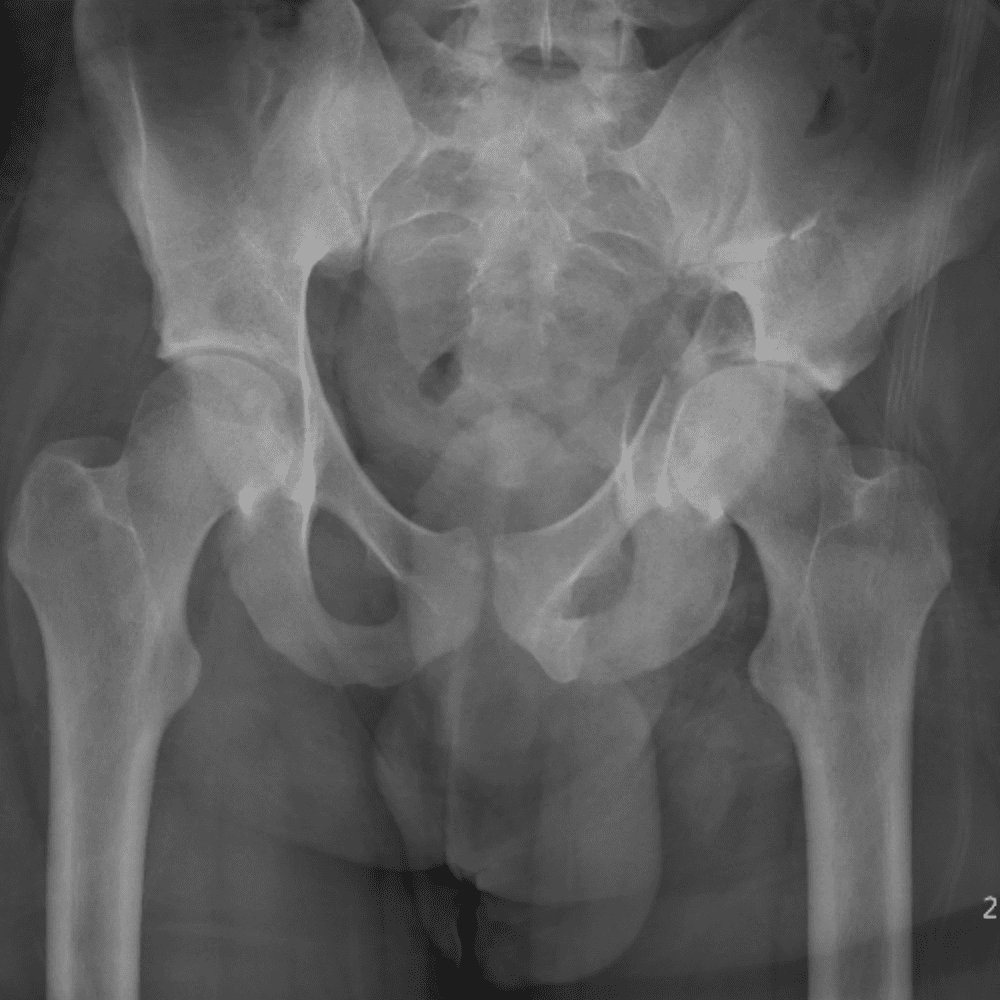

通过包含微妙或困难的病例和一些正常病例来模拟值班。